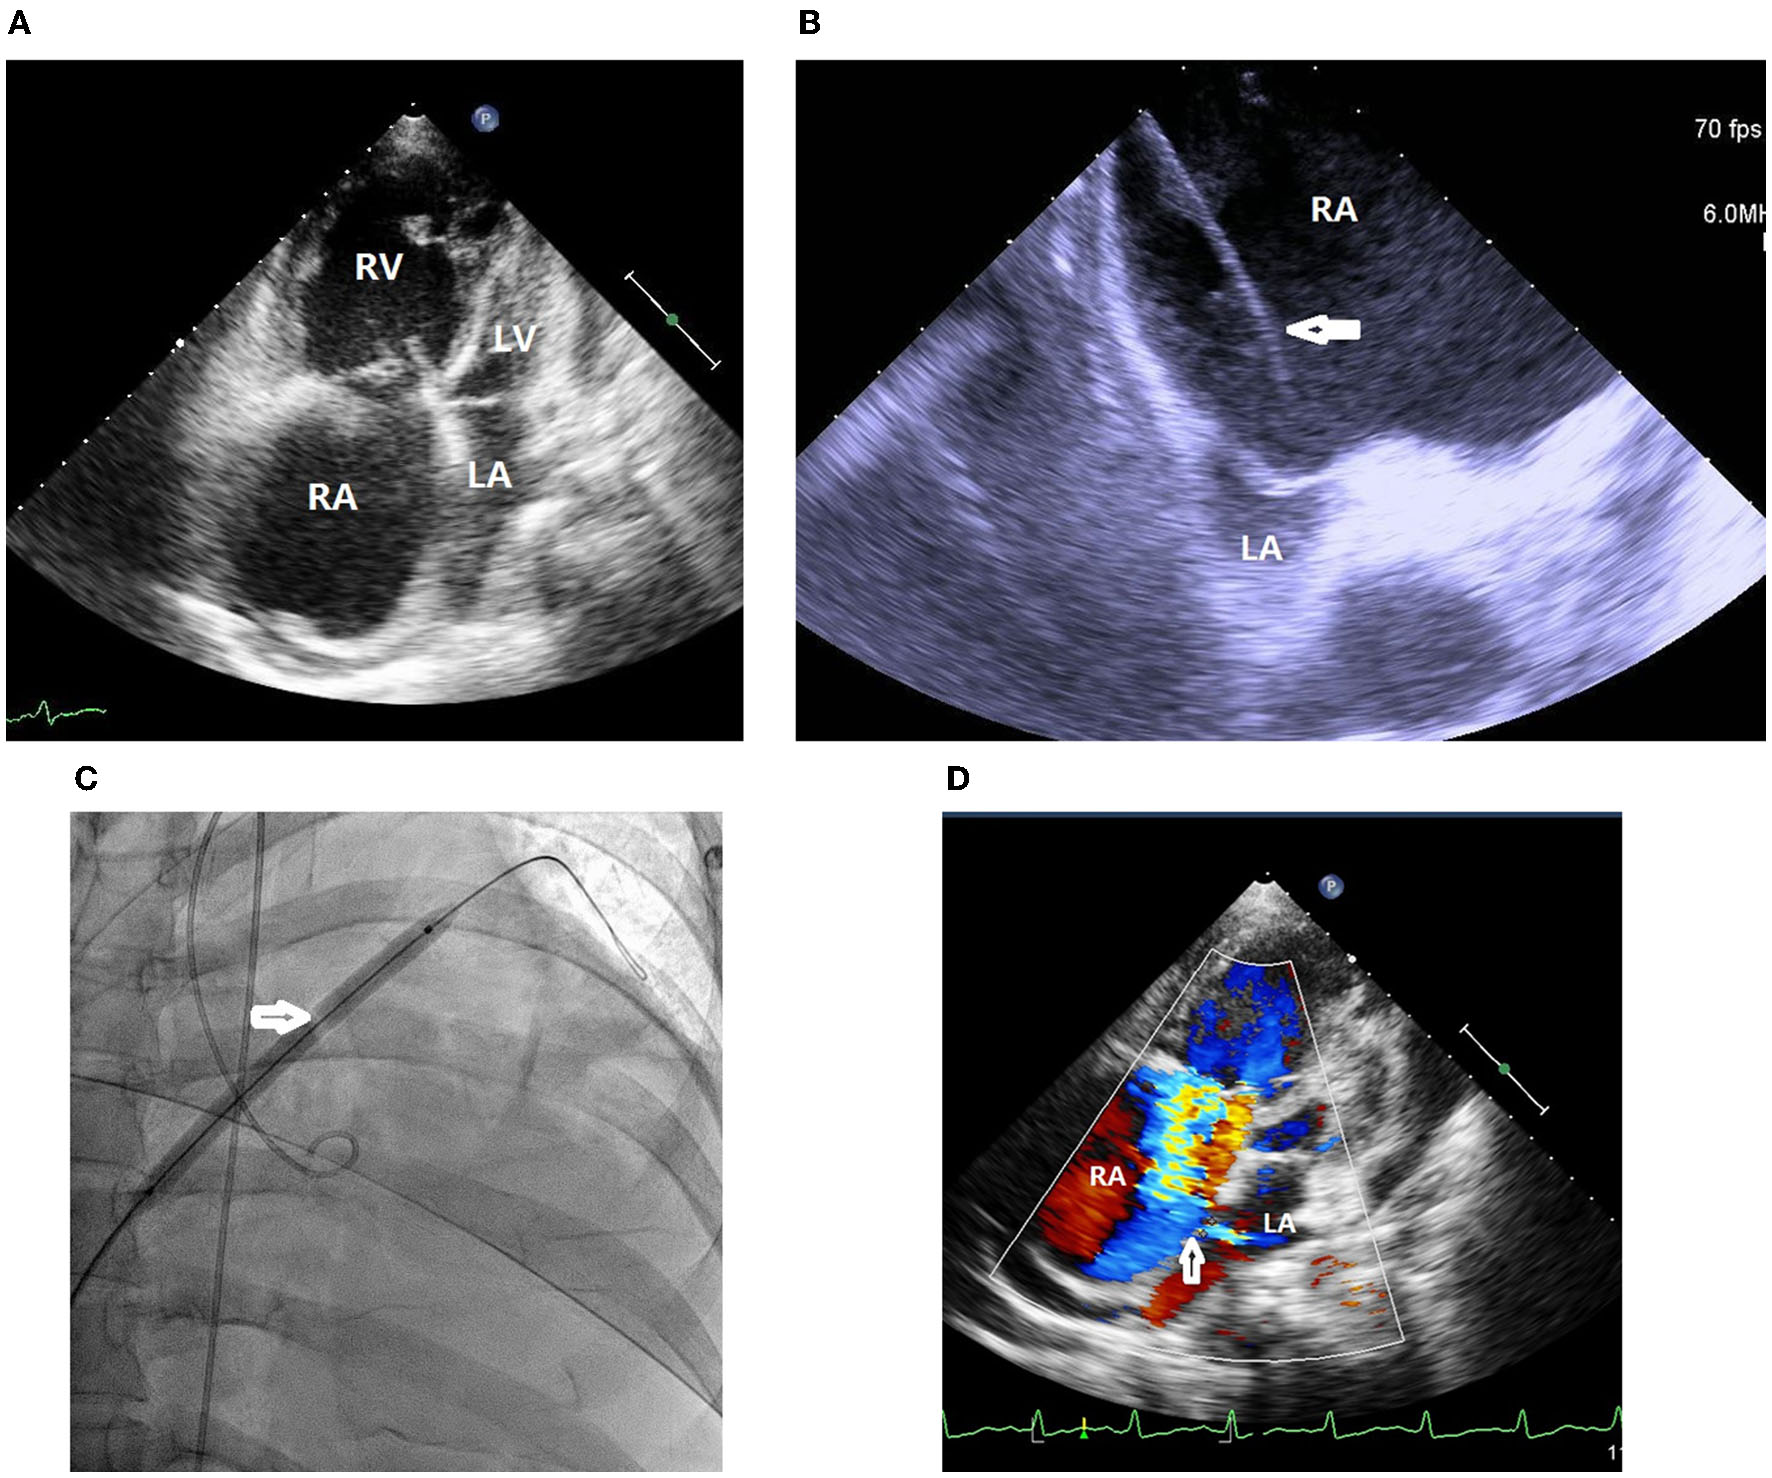

A 37-year-old woman with IPAH had received maximal target medications including oral phosphodiesterase type-5 inhibitor, endothelin receptor antagonist, and subcutaneous PA (treprostinil) injection. Other than IPAH, she had no remarkable past medical history. In April 2020, she developed worsening right heart failure with peripheral edema, oliguria, and hypotension (1st index admission). Upon admission, her systolic blood pressure was 92/76 mmHg, pulse rate was 107 beats/min, pulse oximetry was 91% in room air, and respiratory rate 20/min. Physical examinations revealed a jugular venous giant V wave with estimated central venous pressure ≥ 20 cmH2O, a grade II pansystolic murmur, and a palpable heave at the left lower sternal border. Laboratory data showed anemia with hemoglobin 7.8 g/dL, hypokalemia 3.0 mEq/L, and elevated NT-pro BNP of 4,138 g/dL. Trans-thoracic echocardiogram revealed a marked dilated RA and right ventricle (RV), in addition to a small and compressed left atrium (LA) and left ventricle (LV) (Figure 1A). She had a transition of subcutaneous to IV PA injection via a peripherally inserted central catheter (PICC) and was registered for a lung transplantation waiting list. On the 7th day of admission, we performed standard right and left heart catheterization. The baseline mean RA pressure was 14 mmHg, aortic oximetry was 96% under oxygen supply at 3 L/min through a nasal cannula, systemic CO was 2.9 L/min, and systemic OD was 291 cc/min (Table 1). An intracardiac echocardiogram (ICE) catheter (AcuNac catheter, Siemens, Mountain View, CA, USA) was introduced via the left femoral vein into RA, and the image was displayed on an ACUSON SC 2000 System (Siemens, Mountain View, CA, USA). Using real-time ICE guidance, the inter-atrial septum and fossa ovalis were clearly visualized. We used a transseptal Brockenbrough needle and a Mullins sheath (Medtronic, Minneapolis, MN, USA) to probe the inter-atrial septum before entering the LA cavity under ICE guidance (Figure 1B). The atrial septum was subsequently dilated with a 5 mm × 8 cm and 6 mm × 8 cm Mustang balloon (Boston Scientific, MA, USA) (Figure 1C). After BAS, systemic CO was increased to 3.5 L/min and OD to 318 mL/min, while the systemic arterial oxygen saturation was dropped down to 87% (under nasal cannula 3 L/min oxygen supply) (Table 1). However, we observed no immediate fall of the RA pressure (Table 1). Transthoracic echocardiogram confirmed the establishment of an inter-atrial shunting from right to left (Figure 1D). After BAS in conjunction with continuous IV PA infusion, her heart failure symptoms were alleviated to function II. Her symptoms remained stable thereafter. One and a half years later, she was re-admitted for changing the PICC and to receive cardiac catheterization again as well. ICE confirmed the presence of an interatrial shunt created by previous BAS (Figure 2A). The second baseline hemodynamic data revealed mean RA pressure of 5 mmHg, LA pressure of 2 mmHg, and systemic CO of 3.3 L/min and OD of 403 mL/min. The findings were in support of the sustained hemodynamic improvements (Table 1). The second course of BAS was done with an 8 mm balloon (Figure 2B). ICE showed increased shunting from right to left after the second BAS (Figure 2C). Post second BAS catheterization measurements revealed mean RA pressure of 3 mmHg, LA pressure of 3 mmHg, systemic CO 3.4 L/min, and OD of 420 cc/min (Table 1). She was discharged with stable functional II symptoms.

Figure 1

(A) Trans-thoracic echocardiogram revealed marked dilated right atrium and right ventricle in addition to small and compressed left atrium and left ventricle. RA, right atrium; RV, right ventricle; LA, left atrium; LV, left ventricle. (B) Intracardiac echocardiogram (ICE) showed marked dilated right atrium and small compressed left atrium. A transseptal Brockenbrough needle and a Mullins sheath (white arrow) was probing the inter-atrial septum with a tenting sign. RA, right atrium; LA, left atrium. (C) The atrial septum was dilated with a 6 mm × 8 cm balloon (white arrow). (D) Transthoracic echocardiogram confirmed the establishment of an inter-atrial shunt from right to left (white arrow). RA, right atrium; LA, left atrium.

For this patient, we added procedural refinements to improve the safety and efficacy of BAS. First, we followed the existing guidelines and literature to perform a graded septum dilatation (1, 6, 10). Our patient received 5, 6 mm balloon dilatation in the first BAS session and 7, 8 mm balloon dilatation in the second BAS session at an inter-session interval of 1.5 years. Second, the current guidelines and literature suggest avoiding very high-risk scenarios, such as mean RA pressure > 20 mmHg or room air pulse oximetry <85% (3, 6, 10). The patient was treated in line with the current recommendations. Third, we used ICE to guide the interatrial septum puncture, providing an instant clear view of the septum tenting sign (Figure 1B) and sparing the need for transesophageal echocardiogram and tracheal intubation (4, 5).